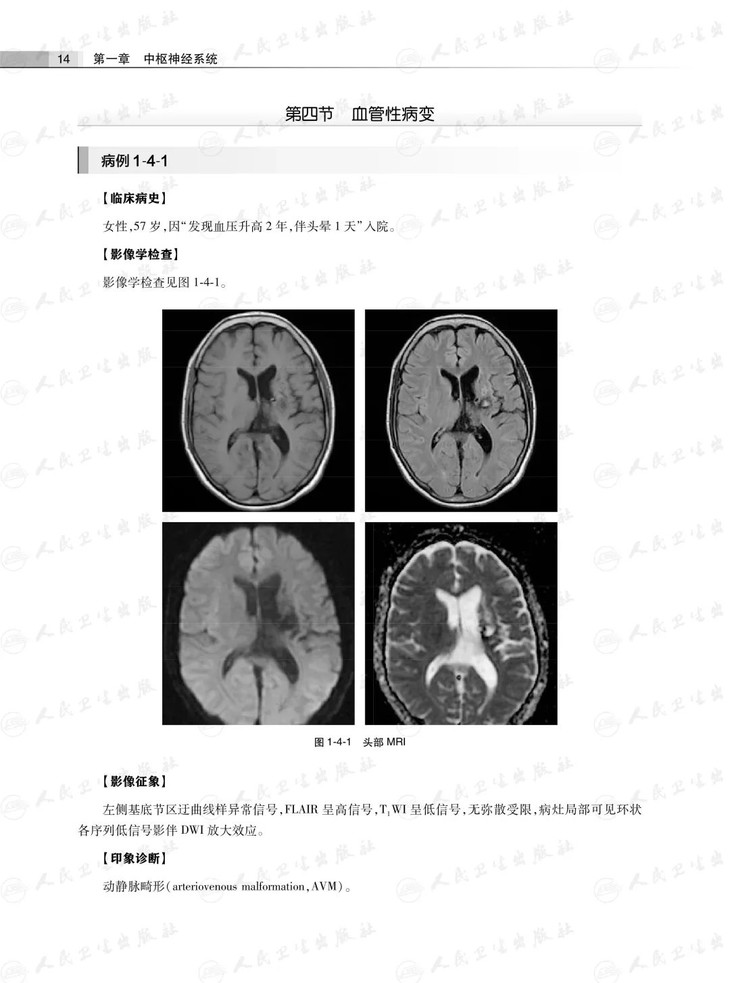

第四节血管性病变